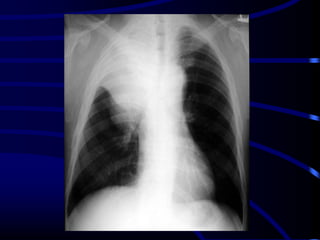

This is the same concept

as a silhouette sign. If

you can recognize the

interlobar pulmonary

artery, it means that the

mass seen is either in

front of or behind it.

This is an example of a

dissecting aneurysm.